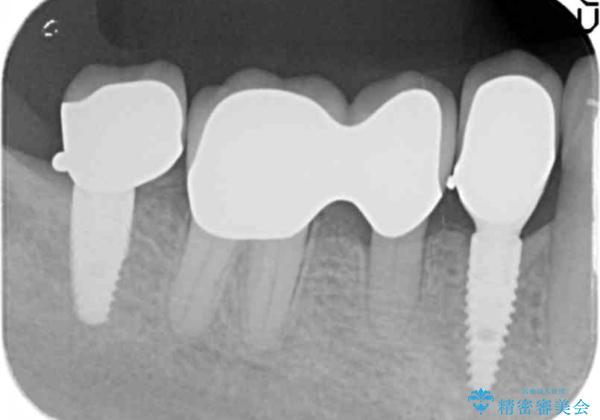

[ 臼歯部インプラント治療 ] 抜けた歯を治療したい

- 抜け落ちた歯と、残った歯の揺れの治療を希望され来院されました。

インプラントを埋入するために

① 不十分な顎骨量 → インプラント埋入と同時に骨の造成

② 角化歯肉の不足 → 遊離歯肉移植術

③ 歯の揺れ → 残存歯の連結補綴

を行う治療計画を立案します。

ただ歯のないところにインプラントを入れて、終わり。と言った治療ではなく、長期的に安定した咬合状態を保てるような噛み合わせの整備や清掃しやすいような歯周環境を整えることで良好な治療結果を得ることができました。